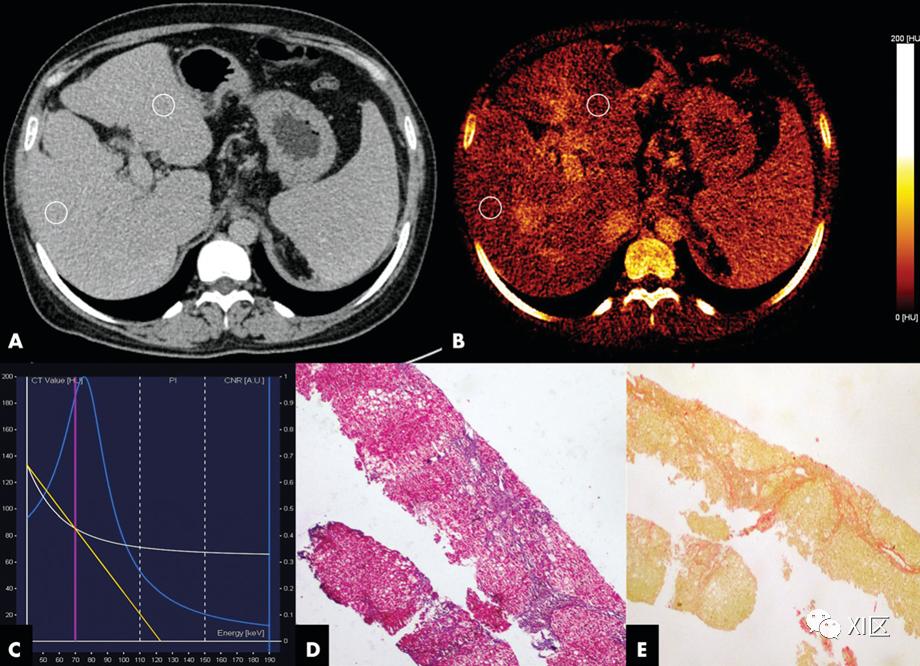

已经尝试使用双能CT数据来估计肝纤维化的程度。据报道,根据碘密度图像计算的细胞外体积分数(ECV)有助于估计肝纤维化的程度。此外,CT纹理分析,如不同能量水平下的灰度强度、偏度、峰度和熵,有助于诊断具有临床意义的肝纤维化。这些参数有望成为肝纤维化的生物标志物;然而,临床检查需要进一步的研究。

图20 26岁女性自身免疫性肝炎患者的图像。A、轴位延迟期肝脏双能CT(DECT)图像,在两个叶中都有感兴趣区域(ROI)。碘浓度在右叶分别为0.9、0.8和0.9 mg/mL,左叶分别为0.9、0.7和1 mg/mL。在腹主动脉中,碘浓度为2.4 mg/mL。肝脏右叶和左叶的标准化碘浓度分别为0.38和0.29。B、延迟期碘图显示肝脏中碘摄取不均匀。C、DECT能谱曲线。白线代表感兴趣区的CT值随能量变化的曲线。黄线是检查中测得的能谱曲线的斜率,为1.29 HU/keV。D、活检样本的显微照片(Masson三色染色;原始放大倍数,340)显示了METAVIR F3期纤维化。E、显微照片(天狼星红染色;原始放大倍数,340)显示胶原比例为6.7%。瞬态弹性成像显示肝脏硬度为13.5 kPa,横波弹性成像显示为13.4 kPa。有效原子序数和电子密度